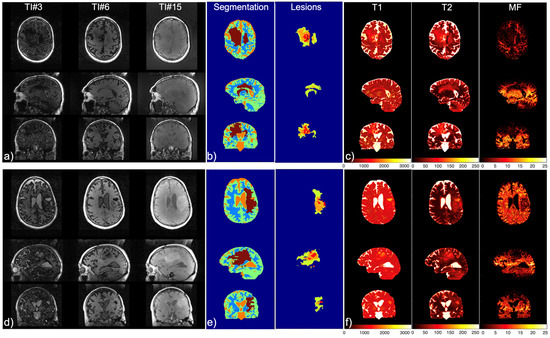

| Mapping | WM | GM | T2L-1 | T2L-2 | CEL | NEC |

|---|---|---|---|---|---|---|

| 2D T1 (ms) | 1186.4 ± 110.5 | 1589.5 ± 331.7 | 1451.5 ± 317 | 1657.9 ± 409.3 | 1947.8 ± 465.6 | 2022.3 ± 459.3 |

| 2D T2 (ms) | 90.4 ± 2.7 | 117.5 ± 12.8 | 114.7 ± 14.2 | 138.2 ± 21.3 | 153.4 ± 47.6 | 152.0 ± 41.1 |

| 3D MWF (%) | 30.4 ± 3.4 | 9.5 ± 3.3 | 12.5 ± 9.3 | 2.3 ± 1.8 | 0.55 ± 0.4 | 0.15 ± 0.0 |

| IIR-bSSFP T1 (ms) | 797.5 ± 88.3 | 670.4 ± 60.2 | 610.9 ± 58.1 | 598.4 ± 77.8 | 958.8 ± 204.9 | 1876.7 ± 608.8 |

| IIR-bSSFP T2 (ms) | 22.0 ± 5.7 | 85.2 ± 8.8 | 62.9 ± 26.5 | 115.4 ± 11.2 | 121.5 ± 10.1 | 157.5 ± 42.0 |

| IIR-bSSFP MF (%) | 14.9 ± 2.5 | 8.7 ± 1.9 | 11.9 ± 3.8 | 5.5 ± 2.6 | 3.6 ± 2.0 | 1.6 ± 0.5 |

| Mapping | CSF | WM | GM | T2L-1 | T2L-2 | CEL | NEC |

|---|---|---|---|---|---|---|---|

| IIR-bSSFP T1 (ms) | 2990.4 ± 277.4 | 848.0 ± 135.5 | 912.4 ± 218.4 | 749.5 ± 217.2 | 883.8 ± 238.8 | 1300.7 ± 303.4 | 2696.6 ± 749.7 |

| IIR-bSSFP T2 (ms) | 218.1 ± 14.9 | 28.5 ± 5.3 | 83.1 ± 20.9 | 62.2 ± 22.4 | 94.1 ± 29.1 | 115.8 ± 19.1 | 190.7 ± 31.9 |

| IIR-bSSFP MF (%) | 1.0 ± 0.4 | 10.0 ± 2.8 | 5.3 ± 1.3 | 7.8 ± 3.4 | 3.4 ± 1.3 | 2.6 ± 1.0 | 2.2 ± 1.2 |